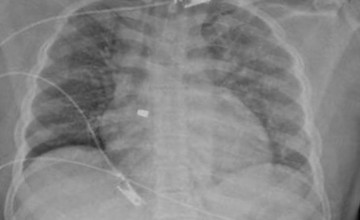

تمكن فريق طبي من قسم الجراحه العامه بمستشفى أملج التابع للتجمع الصحي بتبوك من إنقاذ حياة مقيم إثر تعرضه لإصابة بالرقبة نتيجة آله حادة حيث وصل إلى قسم الطوارئ وهو بحالة صحية حرجة وعلامات حيوية غير مستقرة وذلك بسبب النزيف وتم اجراء الاسعافات الاولية له كذلك الفحص السريري والاشعاعي وتبين وجود نزيف شرياني .

وقال الفريق الطبي المعالج بانه تم على الفور ادخاله لغرفة العمليات وأجريت له عملية استكشاف اتضح وجود قطع في الرقبه بطول 20 سم تقريبا وقطع في طبقات الجلد وقطع في طبقة عضلات الرقبه والاورده الرئيسيه .

واكد الفريق الطبي بأنه تم السيطرة على النزيف وأعطي المريض المحاليل الوريدية والدم كذلك تم ترميم الاورده المصابه والعضلات وتكللت العملية بفضل الله بالنجاح واستغرق إجراء العملية أكثر من ساعتين تم بعدها نقله للتنويم بقسم العناية المركزه وتعويضه بكمية الدم اللازمة وتمت متابعة المريض حتى استقرت حالته وغادر المستشفى بعد أن تماثل للشفاء .